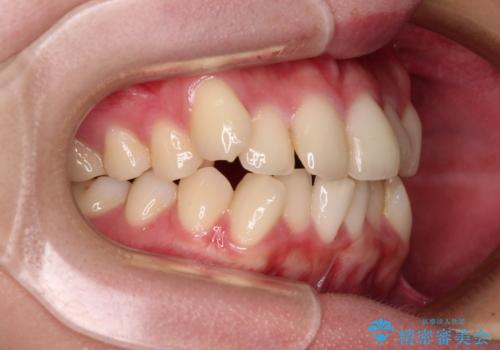

- 八重歯やクロスバイトを気にして来院された患者様です。

口元の突出感はありませんでしたが、デコボコが強く、非抜歯矯正とすると出っ歯仕上がりとなる可能性があったため、上下左右の第一小臼歯4本を抜歯し、ワイヤー装置にて矯正治療を行うこととしました。

デコボコがスッキリするだけでなく、口元の突出感も少し改善され、満足のいく仕上がりとなりました。